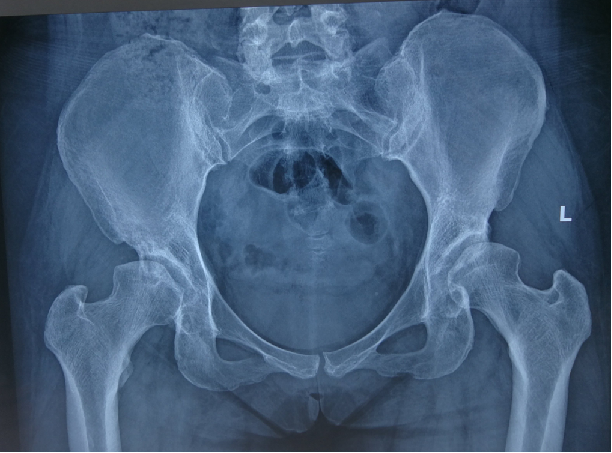

患者,女性,59岁。因“跛行30余年,加重并右髋部疼痛2年”来诊。体格检查:双下肢不等长,右侧髋关节深压痛,双侧髋关节活动受限,右侧显著;右髋关节活动度:屈80°,伸-10°;内收10°,外展20°;内旋:10°,外旋10°;双下肢无明显短缩。患者以右侧髋部疼痛、活动受限为主,左侧无明显疼痛感,给予行右侧全髋关节置换术治疗。

术前X线及髋关节CT图像显示,双侧髋臼明显发育不良,髋臼变浅,右侧髋臼骨质密度不均匀,双侧髋臼对股骨头的包容不足。